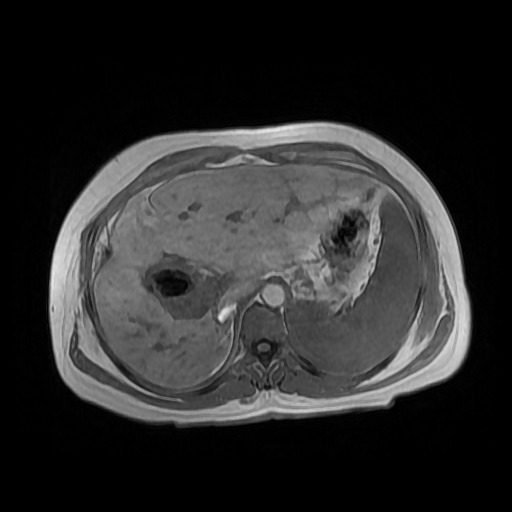

Paciente de sexo femenino, de 56 años de edad, refiere dolor en cuadrante superior derecho, indica que le realizaron colecistectomía de hace mas o menos 7 años, presenta cuadro de ictericia de 6 meses de evolución. Médico tratante le solicita estudio de Resonancia de vías biliares (Coilangioresonancia)

Se prepara a paciente previo a ingreso a zona 4 del área de resonancia magnética, paciente se presenta con catéter en región anterior del antebrazo, se utiliza bobina de abdomen de 16 canales y se procede a obtener localizadores en los tres planos, para luego adquirir imágenes en diferentes planos, en secuencias espin echo, eco de gradiente, secuencia de difusión. Se utiliza medio de contraste hepatoespecifico con dosis sugerida por fabricante.

HALLAZGOS IMAGENOLOGICOS

Se observa dilatación de las vías intra hepáticas a expensas de sus ramas hepáticas derecha, anterior y posterior, hepática izquierda y hepática común. El hepático común da la apariencia de estar anastomosado a un asa de intestino, lo que sugiere la posibilidad de una cirugía entero biliar.

No se logra observar el colédoco.